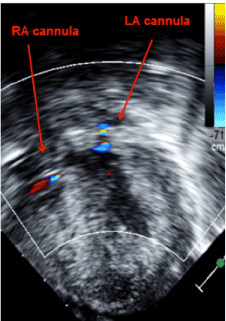

On POD 3 she was listed for heart transplant and on POD 4, she was placed on a continuous flow BiVAD (Figures 2,3). Given right ventricle hypertrophy, and a normal, non-dilated left ventricle, Berlin cannulae were places in the left and right atrium following atrial septal defect closure. Outflow cannulae were attached to the native ascending aorta and pulmonary artery transannular patch. The transannular patch was then ligated proximal to the cannula to prevent backflow of blood moving through the ventricular assist device as no pulmonary valve was present. Next, bypass was weaned onto biventricular continuous flow devices. The left ventricular assist device was run at 150cc/minute of higher flow to make up for the increased pulmonary venous return secondary to multiple collateral vessels present after her prolonged hypoxic state. She tolerated the procedure well, but continued to suffer from persistent ventricular arrhythmias.

Figure 3:Transgastrictransesophageal echocardiogram demonstrating appropriate decompression of the ventricles using continuous flow biventricular ventricular assist devices.  Inflow cannulas visualized in the right and left atrium.